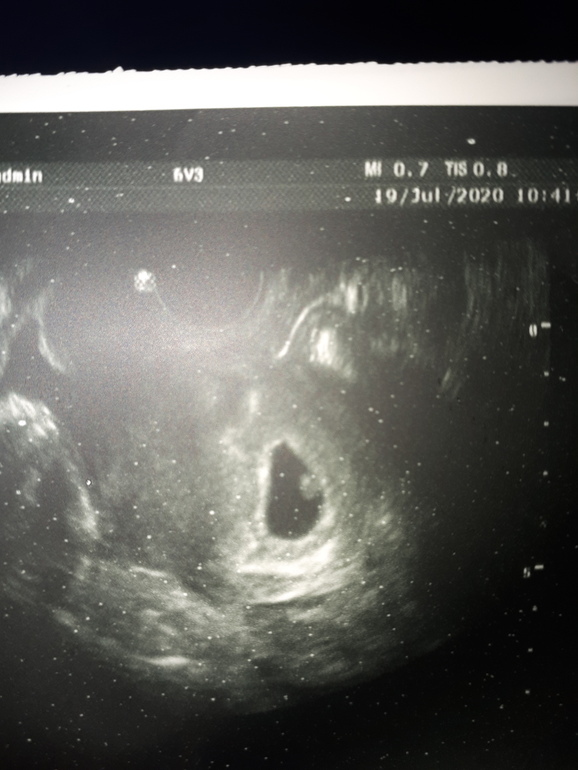

Была сегодня на узи, срок 6+4, крохотулечка в матке, чсс 117, все в норме (как сказал узист) ПЯ 20мм, КТР 5мм

По прикреплению хориона и эмбриончика,у вас он справа,если трансвагинально,то справа на девочку,слева на мальчика,если по животу то наооброт,метод не 100% ,но на 70 % совпадает,у меня совпало два раза